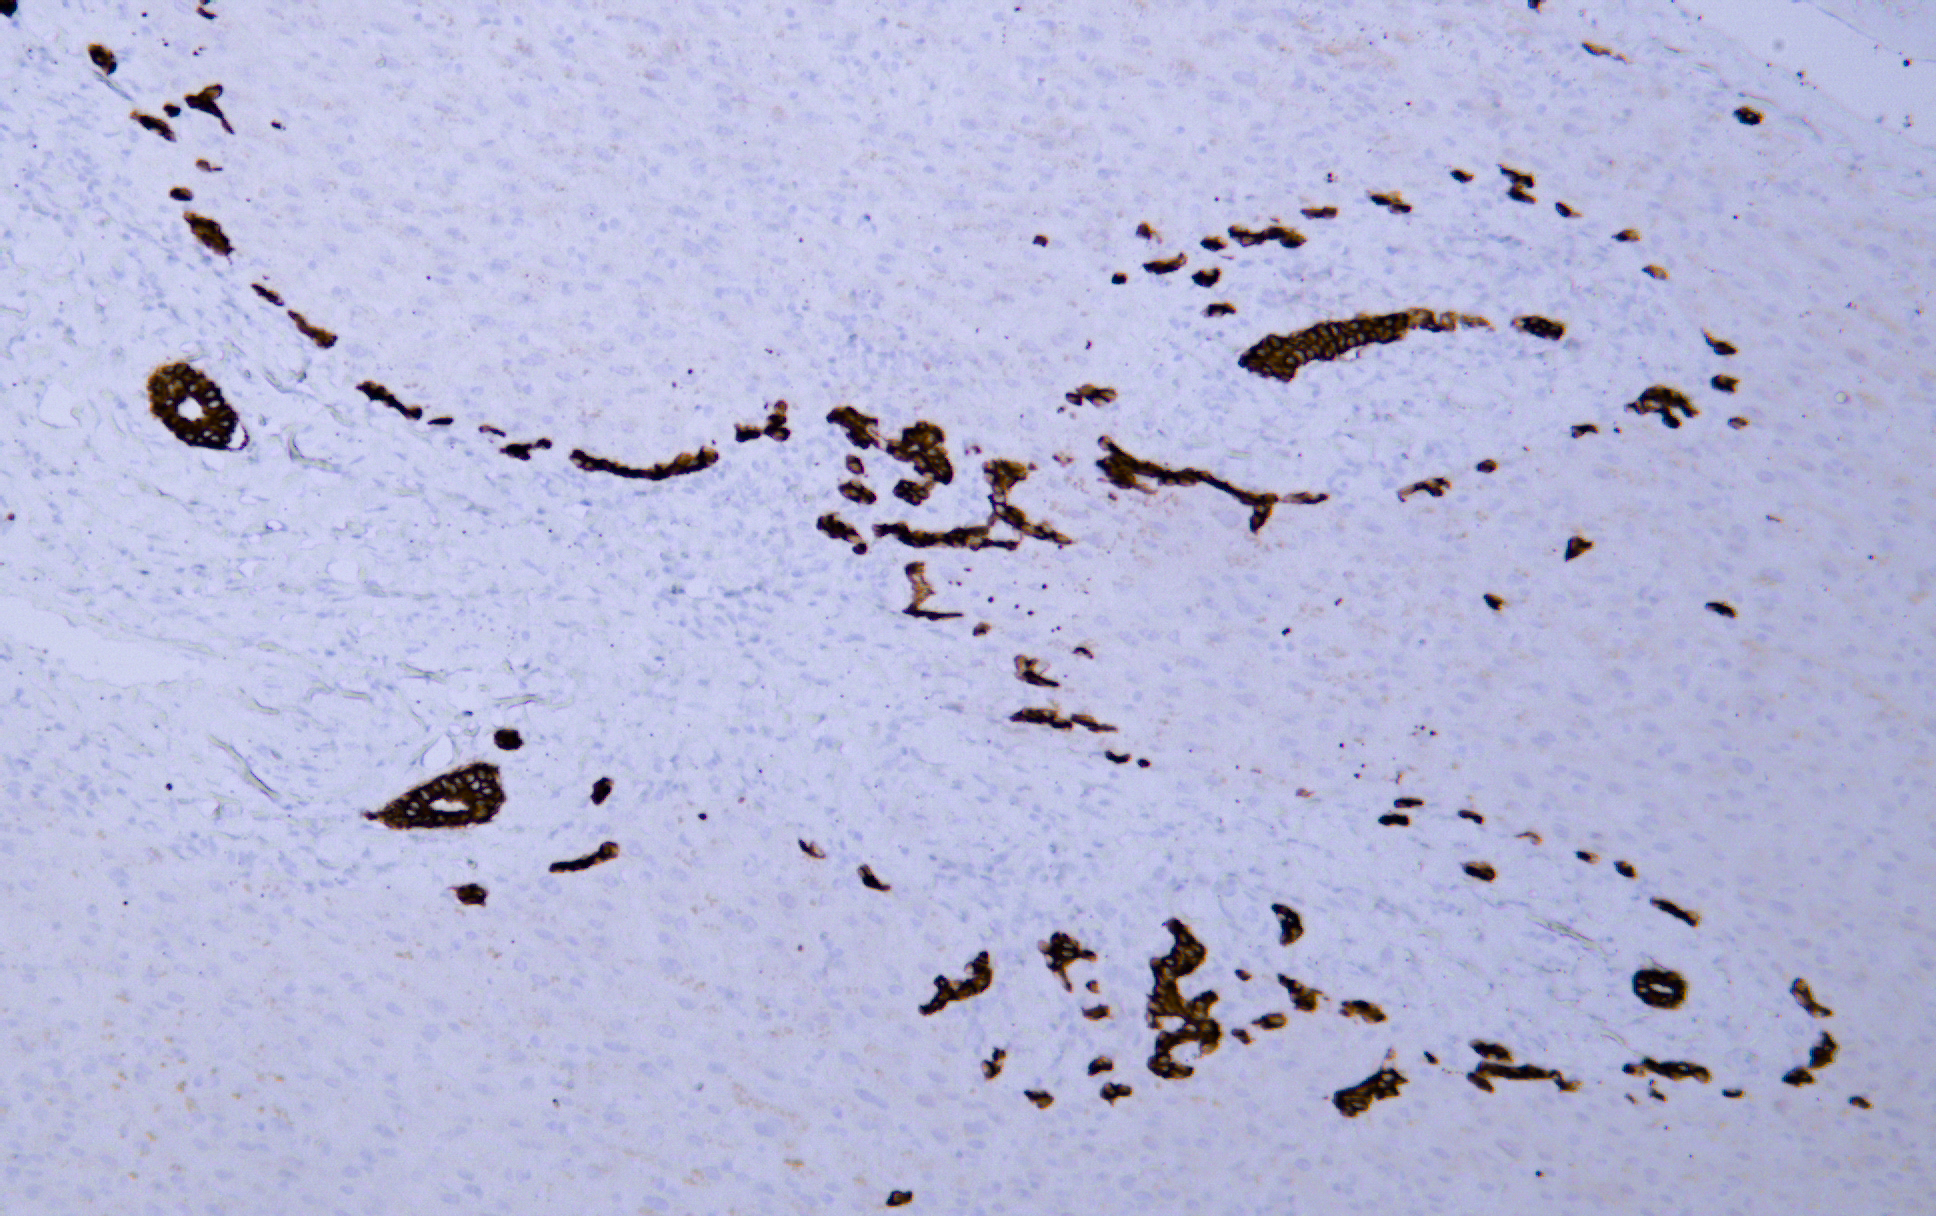

Cytokeratin 7 (AB1432) mouse mAb

CK7 is a cytokeratin with a molecular weight of 54 kDa, which mainly marks glandular epithelium and transitional epithelium. It was positive in the epithelium of breast, thyroid, ovary, endometrium and lung, but negative in the epithelium of gastrointestinal tract, colon and prostate. It is mainly used for the study of epithelial tumors. It is often used in combination with CK20 for differential diagnosis of gastrointestinal adenocarcinoma, lung adenocarcinoma and breast cancer, and combined with EMA for diagnosis of synovial sarcoma.

IHC, 1:200-1:1000 | WB, 1:500-1:2000 | IF, 1:100-1:500 | ELISA, Recommended starting concentration is 1 µg/mL. Please optimize the concentration based on your specific assay requirements.

Specificity

The antibody can specifically recognize human CK7 protein, and shows no cross reaction with CK1, 4, 5, 6, 8, 10, 14, 17, 18, 19, 20. In western blotting of Hela, A431, A549 and Hela cell lysates, the antibody can label a 51 kDa band corresponding to CK7 in A549 and Hela cell lysates.